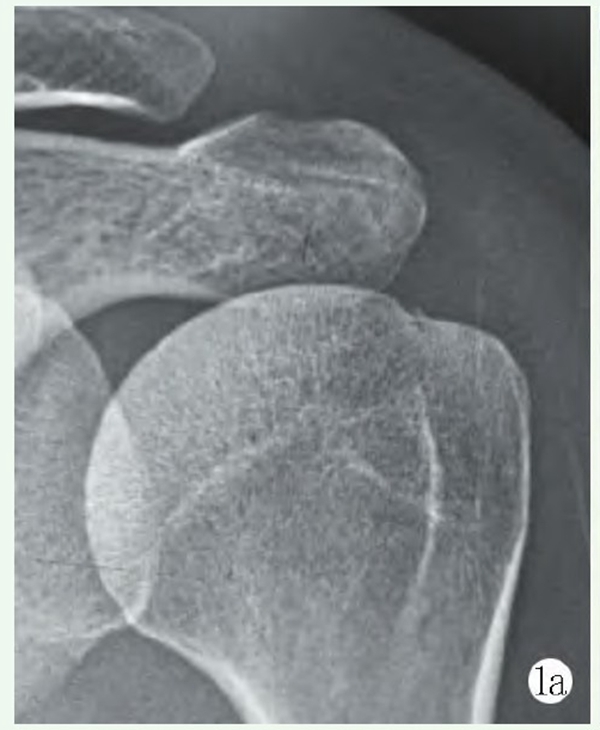

影像学检查:X线片显示左肱骨头解剖颈处小骨片(图1a),彩超示:左肱骨头解剖颈处小撕脱骨片。

图1a:术前肩关节正位 X 线片示左肱骨头解剖颈处小骨片

手术:采用全麻联合臂丛神经阻滞麻醉。右侧卧位左肩外展牵引下手术。左肩关节后方及前方建立关节镜手术入路,关节镜探查盂肱关节见盂唇附着完好,肱骨头关节面边缘冈上肌附着处可见全层软骨及软骨下骨撕脱骨折片5~6mm,冈上肌从肩关节撕裂(图1b)。置入带线锚钉通过Trans-Tendon法用腰穿针将锚钉尾端缝线穿过冈上肌后打结固定骨折块(图1c)。

图1b: 镜下见冈上肌关节面横行撕裂;1c: 置入锚钉,用腰穿针将锚钉尾端缝线穿过冈上肌后打结固定骨折块